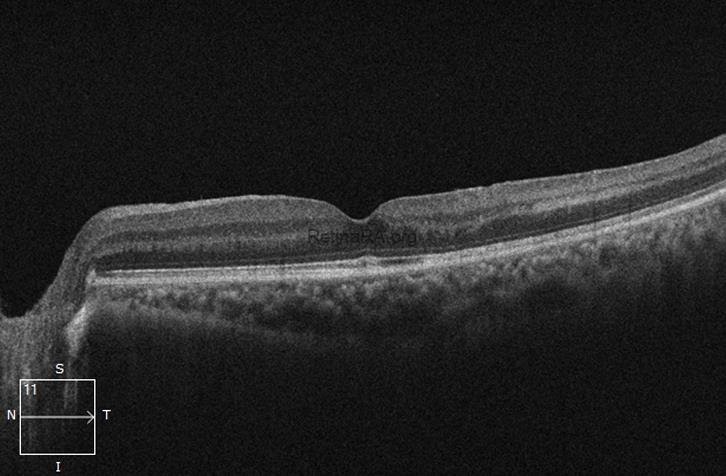

Fundus picture & OCT Scan (Presentation): At presentation depicts nearly arcade to arcade presence of sub hyaloid hemorrhage. OCT scan confirms the large pre-retinal hemorrhage with back shadow masking the underlying entire retinal architecture.

Fundus picture & OCT Scan (Post-intervention): Post-vitrectomy macula appears within normal limit. OCT depicts normal architecture of the retinal layers, with normal foveal thickness and maintained foveal contour.